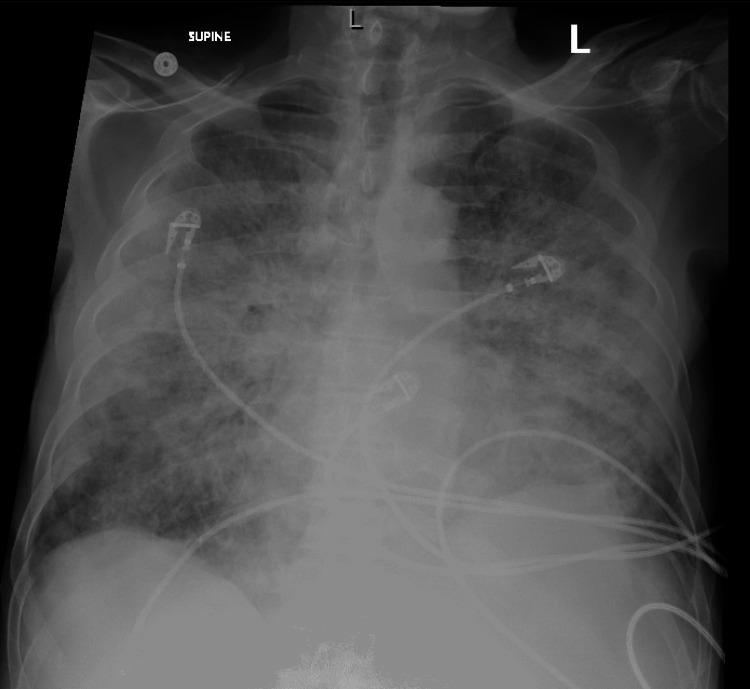

阿扎胞苷诱发的急性髓系白血病合并白细胞增多症患者的肺炎

Azacitidine-Induced Pneumonitis in a Patient With Acute Myeloid Leukemia and Hyperleukocytosis.

Chemotherapy-related toxicity is a complex aspect of oncologic care. Pulmonary toxicity, in particular, poses a significant challenge, as it can have diverse presentations and can closely mimic other common complications of cancer treatment, such as infections. Azacitidine is an agent widely employed in high-risk myelodysplastic syndrome and acute myeloid leukemia. We present a case of azacitidine-induced pneumonitis, a rare adverse effect, in a 70-year-old patient with acute myeloid leukemia (AML) and hyperleukocytosis. After discontinuation of the drug and introduction of steroids, the patient had complete resolution of symptoms, highlighting the importance of identifying and addressing chemotherapy-induced pneumonitis.

摘要